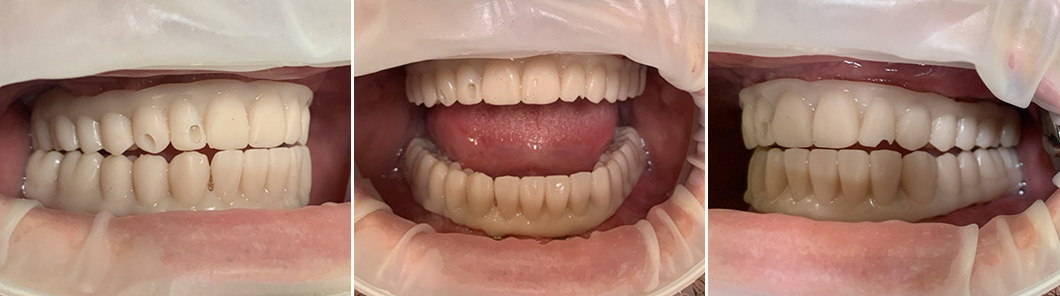

Сначала были изготовлены прототипы двух полных протезов – они нужны для выведения прикуса по буграм: мы добивались правильного соотношения челюстей по высоте. Это важно для того, чтобы исключить перегрузку височно-нижнечелюстного сустава (ВНЧС). С первым прототипом мы не попали в центральное соотношение резцов (линия между центральными передними зубами в верхней челюсти должна совпадать с линией между центральными передними зубами в нижней челюсти). Поэтому прототипы мы переделали и достигли правильного центрального соотношения.

Я провел приточку по буграм – по высоте коронок в каждом протезе, чтобы К. было комфортно. Так мы достигаем ощущения, что это «свои зубы» - ничего не мешает, пациент нормально жует и красиво улыбается. На основании прототипов началось изготовление постоянных протезов. Кстати, пациент К. отказался от ношения временных ортопедических конструкций (из финансовых соображений), так что было проведено сразу постоянное протезирование.

Были изготовлены 2 встречных протеза, опирающиеся на фрезерованные титановые балки. Материал коронок – диоксид циркония: 14 зубов в протезе верхней челюсти и 14 зубов в протезе нижней челюсти. Итого – 28 зубов в 2 полных зубных рядах.